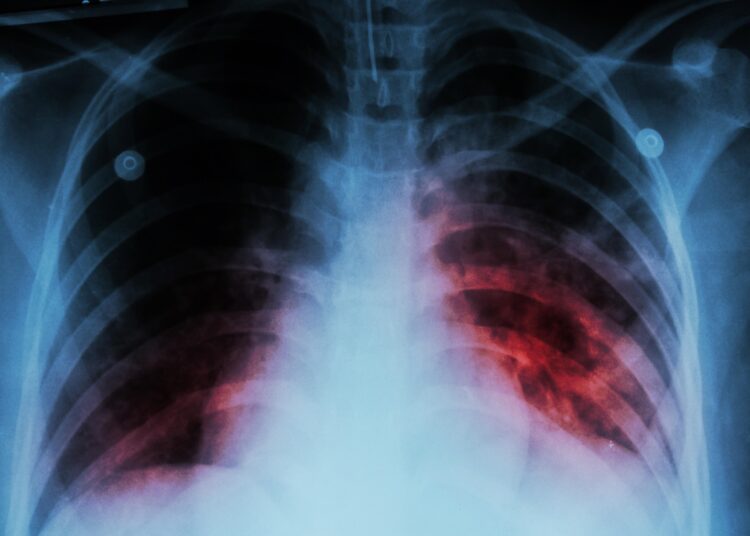

La tuberculosis es una enfermedad infecciosa que se transmite por vía aérea, pero con detección temprana y tratamiento oportuno, puede ser controlada de manera efectiva. En este sentido, la Secretaría de Salud Distrital hace un llamado a la población para que acuda a los centros de salud en caso de presentar síntomas como tos persistente, fiebre, pérdida de peso y sudoración nocturna.